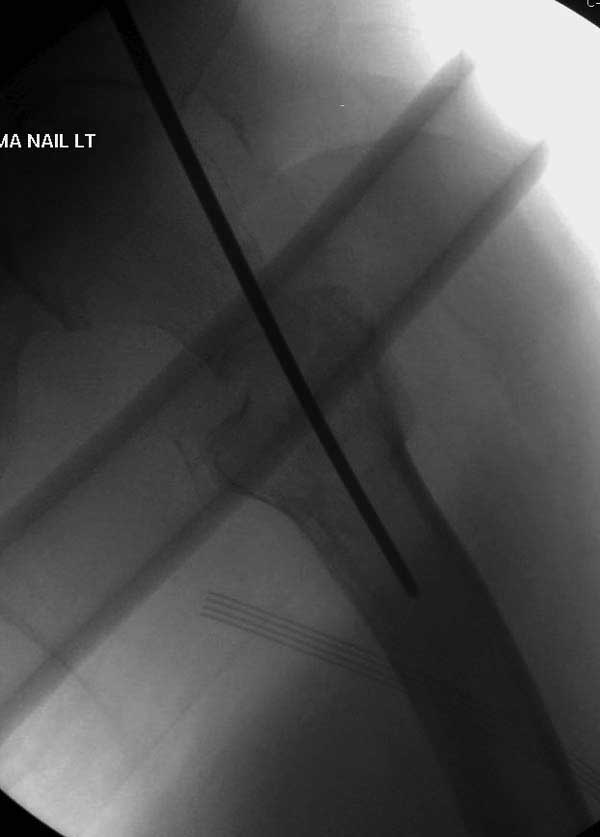

Сеньоры-пэры ревизировали гвоздем, шуруп поставили по той же дорожке, только поглубже. Да еще и bone graft не пожалели. "Результат" уже был через 2 дня.

Если сохранять головку - думаю надо было в валгусе фиксировать перелом гвоздем, или DCS, т.к. все-равно разрезали, чтоб достать DHS.

Вторая операция- это фаза сохранения головки бедра. Желательно приложить все усилия и сохранить головку, но, как видно, “фиаско” продолжается. Здесь вместо нейтрализации сил между медиальной и латеральными сторонами была попытка удержать варус. Варус не удержать ни деротационными шурупами о котором говорили и не костными стружками вбитые в шейку, потому что вся нагрузка упирается в головку.

Как отметил Евгений, 95 degree Blade Plate Fixed Angle device расчитана на восстановление взаимоотношении между головкой и диафизом, а все остальные фиксаторы (Gamma, Afifuxus и др.) работают за счет нагрузки в верхнем полюсе головки. Верхний полюс успели разрушить, и в головке единственное место, который смог бы удержать широкий клинок конструкции, это медиально-низкий сегмент. После установки клинка засчет дистракции можно удлинить конечность на 15мм, а добавленный в дефект ауто-графт закончил бы дело.

Третья операция-продолжения усилии “синьорами пэрами” по разрушению нормальной анатомии. Крест на головку! По видимому возраст позволяет биполярную конструкции, и при дефекте calcar пошли на обычный цементный. Ягодичные мышцы потеряли связь с вертелом, т.е. отсутствует верхний удержатель, и результат “a Big Screw Up!” Снимки вызывают головокружение!